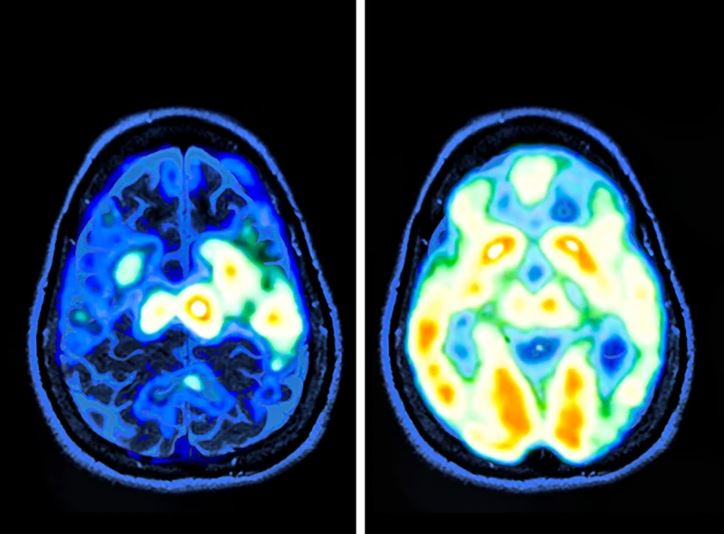

Účinky dlhodobého bdenia sa prejavili rýchlo. Tretí deň Randy trpel nevoľnosťou a bojoval so stratou krátkodobej pamäti. Neskoršie skeny mozgu odhalili, že jeho mozog „driemal“ po častiach – niektoré časti sa na krátko vypínali, zatiaľ čo iné zostávali aktívne, čo mu umožňovalo fungovať aj napriek extrémnej vyčerpanosti.